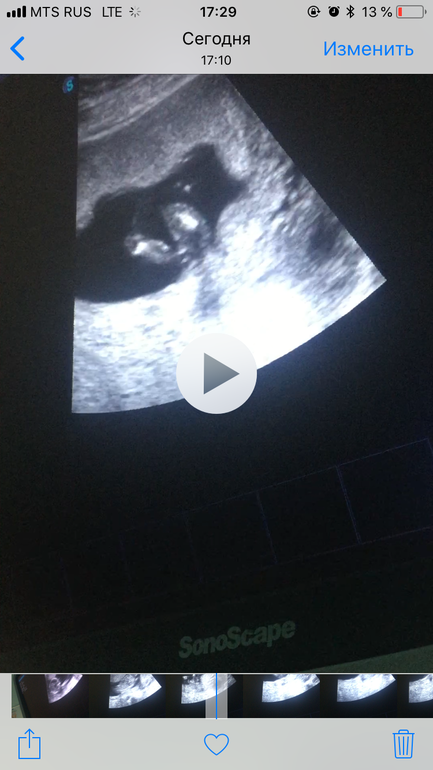

Подтвердили пол))

Изменения и болезни во время БДевочки, вы были правы, как и права мой узист в 11,1 недель))

Ждём Таю или Ульяну))

Девочки, ваши предположения , кто у нас 11,1 пытаюсь разглядеть фото скрины с видео смотришь и не понятно то ли ножка толи бугорок …. Как думаете ???